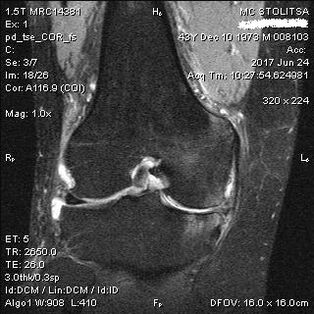

The diagnosis of arthrosis of the knee joint takes place in the office of a rheumatologist or orthopedist.The doctor examines the affected joint, fixes it, listens to complaints and asks additional questions.Perform some tests - for example, asking the patient to bend his leg or walk a few steps.Then, if it is necessary to clarify the extent of the disease or the nature of pathological changes, he will refer you for additional studies.For example, for computed tomography or radiography.